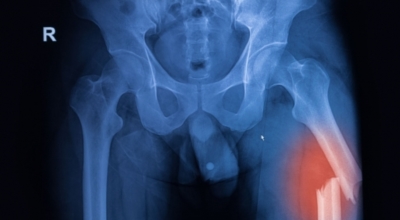

우리나라 사람들이 노년기에 가장 많이 겪는 만성질환은 관절염이라고 하네요. 우리의 육체의 뼈 연골을 구성하는 주요 성분인 콘드로이친이 부족하다 보면 관절통이나 근육의 통증 과 같은 증상이 생겨나게 된다고 합니다. 최근 광고도 많이 나오면서 많은 분들이 궁금해 하시는 콘드로이친 효능에 대해 알아보려고 합니다.

인체의 조직이나 기능을 연구하는 학문에 따르면 사람의 연골에서 콘드로이친의 비율은 출생부터 40세까지 서서히 줄어든다고 합니다. 이것이 바로 연골이 점점 안 좋아지는 원인 중의 한 종류인데요 콘드로이친(연골)을 보충한다는 의미는 하중을 견디는 연골에 영양분을 공급함으로써 마찰력을 줄여주며, 관절이 마모되는 속도를 늦출수 있다는 것을 의미합니다.

한 번 훼손된 무릎 연골은 다시 재생되지 않는다는 특성을 지니고 있으며, 노화로 인해 서서히 감소한 몸 안 콘드로이친은 중년에 이르면 생성할 수 있는 양이 1/20에 불과합니다. 콘드로이친은 자연노화로 인하여 관절, 무릎통증, 연골의 노화진행으로 기인해서 오는 질환에 증상완화를 도와주어 연골세포를 유지시켜줘요. 콘드로이친은 연골세포를 보호해주고 부드럽고 유연하게 지속시켜서 줍니다.

콘드로이친의 가장 가장 저명한 효능 중 한 종류로 관절 건강이 있답니다. 연골이 마모되면서 뼈와 뼈 사이가 좁아져 관절염이 발생하고 통증이 발생되는데 콘드로이친을 먹게 되면 관절염 보완에 도움이 돼요. 마모되어 얇고 연약해진 연골의 내마모성과 볼륨 유지를 이완하여주는 구실을 해서 연골을 지켜주며 염증이 생기게 될 수 있는 관절에 쿠션을 제공해서 통증을 떨어뜨리고 일상생활을 원활하게 하도록 하는데 보탬이 돼요. 콘드로이친을 연속적으로 먹게 되면 관절 건강에 좋습니다.